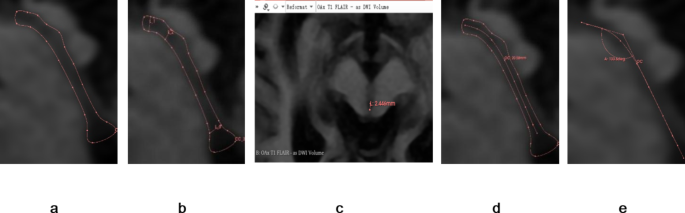

Measurements were conducted systematically in the following steps. First, DICOM-formatted images were imported into the 3D Slicer software and the “Markups” function was used to delineate the approximate shape of the cerebral aqueduct on the “OSag 3D-FIESTA” sequence images (Fig. 1a). The diameters at the opening of the third ventricle, the site of stenosis (typically located 3–4 mm from the surface of the cardiac apex), and the opening of the fourth ventricle (Fig. 1b) were measured. Concurrently, the “Link slice views” feature of 3D Slicer was used to automatically align the “OSag 3D-FIESTA” sequence images with the axial plane images, where the diameter of the cerebral aqueduct was measured again on the axial images (Fig. 1c), ensuring that the measurements obtained in the sagittal and axial planes were consistent. Then, the length of the cerebral aqueduct was measured on the “Sag 3D-FIESTA” sequence images (Fig. 1d). Finally, the angle between the anterior-superior segment and the posterior-inferior segment of the cerebral aqueduct was measured (Fig. 1e).

Analysis of mesencephalic aqueduct morphology on magnetic resonance images of the brainstem. (a) Borders of the mesencephalic aqueduct in the mid-sagittal plane. (b) Diameters of the mesencephalic aqueduct at the rostral opening with the third ventricle, constriction, and termination at the fourth ventricle. (c) Measurement of these same aqueduct diameters in the axial plane using the automatic linkage feature of 3D Slicer. (d) Length of the mesencephalic aqueduct. (e) Angle between the anterior upper and posterior lower segments of the mesencephalic aqueduct. Segments are separated by the constriction (as shown in b).